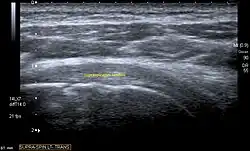

Ultrasound

There are several advantages of ultrasound. It is relatively cheap, does not emit any radiation, is accessible, is capable of visualizing tissue function in real time, and allows the performance of provocative maneuvers in order to replicate the patient’s pain.[28] Those benefits have helped ultrasound become a common initial choice for assessing tendons and soft tissues. Limitations include, for example, the high degree of operator dependence and the inability to define pathologies in bones. One also has to have an extensive anatomical knowledge of the examined region and keep an open mind to normal variations and artifacts created during the scan.[29]

Although musculoskeletal ultrasound training, like medical training in general, is a lifelong process, Kissin et al. suggests that rheumatologists who taught themselves how to manipulate ultrasound can use it just as well as international musculo-skeletal ultrasound experts to diagnose common rheumatic conditions.[30]

After the introduction of high-frequency transducers in the mid-1980s, ultrasound has become a conventional tool for taking accurate and precise images of the shoulder to support diagnosis.[31][32][33][34][35]

Adequate for the examination are high-resolution, high-frequency transducers with a transmission frequency of 5, 7.5, and 10 MHz. To improve the focus on structures close to the skin an additional "water start-up length" is advisable. During the examination the patient is asked to be seated, the affected arm is then adducted and the elbow is bent to 90 degrees. Slow and cautious passive lateral and/or medial rotations have the effect of being able to visualize different sections of the shoulder. In order to also demonstrate those parts which are hidden under the acromion in the neutral position, a maximum medial rotation with hyperextension behind the back is required.[36]

To avoid the different tendon echogenicities caused by different instrument settings, Middleton compared the tendon’s echogenicity with that of the deltoid muscle, which is still lege artis.[37][38]

Usually the echogenicity compared to the deltoid muscle is homogeneous intensified without dorsal echo extinction. Variability with reduced or intensified[39] echo has also been found in healthy tendons. Bilateral comparison is very helpful when distinguishing and setting boundaries between physiological variants and a possible pathological finding. Degenerative changes at the rotator cuff often are found on both sides of the body.[40] Consequently, unilateral differences rather point to a pathological source and bilateral changes rather to a physiological variation.[38]

In addition, a dynamic examination can help to differentiate between an ultrasound artifact and a real pathology.[41]

To accurately evaluate the echogenicity of an ultrasound, one has to take into account the physical laws of reflection, absorption and dispersion. It is at all times important to acknowledge that the structures in the joint of the shoulder are not aligned in the transversal, coronal or sagittal plane, and that therefore during imaging of the shoulder the transducer head has to be held perpendicularly or parallel to the structures of interest. Otherwise the appearing echogenicity may not be evaluated.[42]

![]() |